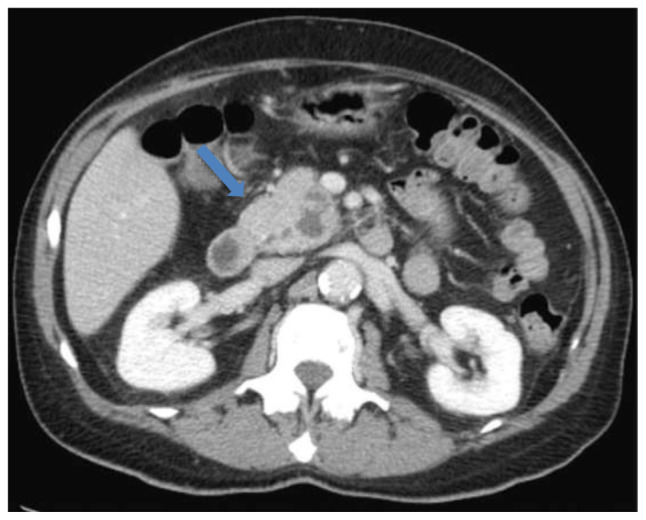

一位67岁男性患者,在过去的三个月里表现为厌食、体重减轻、皮肤肿块和腹部疼痛。影像学显示肺肿块及胰头囊性病变。在最初的诊断检查和临床恶化后,在病理上看到广泛的芽殖,导致播散性芽殖菌病的诊断。患者接受两性霉素B脂质体治疗14天后,再加伊曲康唑治疗,临床表现明显改善。我们回顾了医学文献中所有涉及胃肠道器官的播散性芽孢菌病病例。虽然胰腺受累是罕见的,我们建议应该怀疑那些快速增长的胰腺肿块,即使是免疫功能正常的患者。最后,应迅速进行组织活检,但如果初步结果为阴性且临床怀疑仍然很高,则可能需要重复活检。

A 67-year-old male patient presented with anorexia, weight loss, skin masses, and flank pain over the past three months. Imaging revealed a lung mass and a cystic lesion in the pancreatic head. After initial diagnostic work-up and clinical deterioration, broad based budding, seen on pathology, led to a diagnosis of disseminated blastomycosis. After receiving a 14-day course of liposomal amphotericin B followed by itraconazole, the patient showed significant clinical improvement. We reviewed all disseminated blastomycosis cases in the medical literature involving gastrointestinal organs. Although pancreatic involvement is rare, we suggest that it should be suspected in those with a rapidly growing pancreatic mass even in immunocompetent patients. Finally, tissue biopsy should be obtained expeditiously, but repeat biopsy may be indicated if initial results are negative and clinical suspicion remains high.